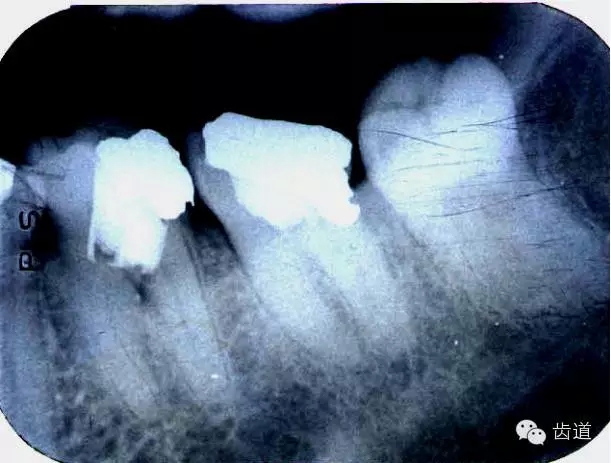

磨牙髓室頂、底距離接近時,易將髓底穿孔。

左下6底穿

左上6底穿